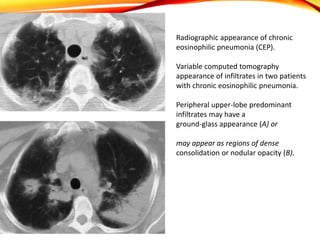

Carrington and colleagues described three radiographic features that are

characteristic for CEP:

(1) peripherally based, progressive dense infiltrates;

(2) rapid resolution of infiltrates following corticosteroid treatment, with

recurrences in identical locations; and

(3) The appearance of infiltrates as the “photographic negative of pulmonary

edema.

Radiographic appearance of chronic

eosinophilic pneumonia (CEP).

Variable computed tomography

appearance of infiltrates in two patients

with chronic eosinophilic pneumonia.

Peripheral upper-lobe predominant

infiltrates may have a

ground-glass appearance (A) or

may appear as regions of dense

consolidation or nodular opacity (B).

Radiological findings

• Infiltrates are bilateral, mid- to upper lung zones, and may mimic loculated

pleural fluid.

• The areas of consolidation are patchy and dense and can have ill-defined

margins.

• The characteristic “photographic negative of pulmonary edema” appearance

(which occurs in less than 50 percent of cases) results if extensive infiltrates

surround major portions of or the entire lung.

• Common CT scan findings include ground-glass opacities without clear

consolidation.

• Mediastinal lymphadenopathy may be present.